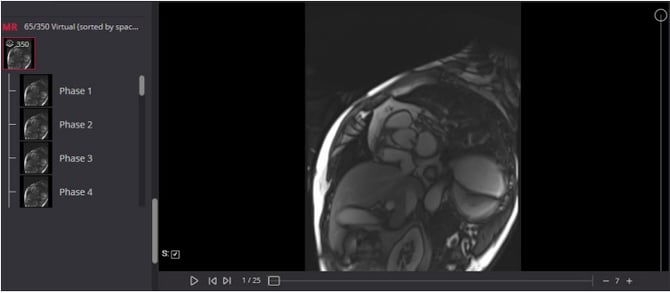

4D Tools – Create a Virtual 4D Series

4D tools allow dynamic review across time and space. Merge related series into a virtual 4D series for a comprehensive dynamic assessment.

Constructing a Virtual 4D Series

- Select the desired series from the viewer thumbnail.

- Click Construct 4D Series.

- Mark the required related series and press Create (the study will preload if not already loaded).

- A new "Virtual" series thumbnail will be added to the viewer list at the bottom

- The virtual series remains active until the session ends.

Navigating the 4D Tool

- ⏯️ Play / Pause: Start and stop frames at the set speed.

- Adjust Frame Rate: Use the ➖ and ➕ buttons to change the play speed.

- Horizontal Slider: Adjusts the image by time points.

- Vertical Slider: Adjusts the image by location.